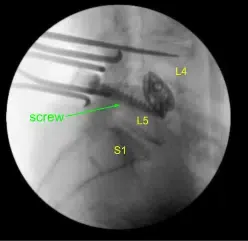

Dada la preocupación por el implante en posición prona y la sensación de que las placas terminales podrían haberse fracturado más, expusimos los procesos transversales de L4 y L5 y usamos el taladro para crear agujeros piloto en el pedículo del lado izquierdo en L4 y L5. Bajo fluoroscopia, guiamos las sondas a través de los pedículos y tocamos cada pedículo, luego colocamos tornillos pediculares en L4 y L5.

Estos tornillos se estimulaban y se comprobaban mediante fluoroscopia, luego se colocaba una roda y se apretaban finalmente los tornillos de tapa. En el lado derecho e izquierdo, decoricamos las facetas y procesos transversales y colocamos nuestra masa de fusión para la artrodesis.